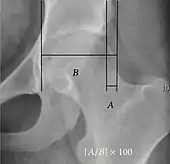

- Reimer's migration index (MI), also called the femoral extrusion index,[3] is calculated if hip dysplasia is detected. It can be used to indicate hip dislocation. It is the horizontal distance (parallel to the Hilgenreiner Line) between the Perkin line and the lateral border of the ossification center of the femoral head, divided by the horizontal width of the ossification center. The migration index is normally less than 33% by most sources,[9] but 25% and 30% has also been suggested.[10]

| Reimer's migration index[9] | ![]() |

The percentage of the femoral head that lies outside of the acetabular roof. It is also called the femoral extrusion index. | <25% |